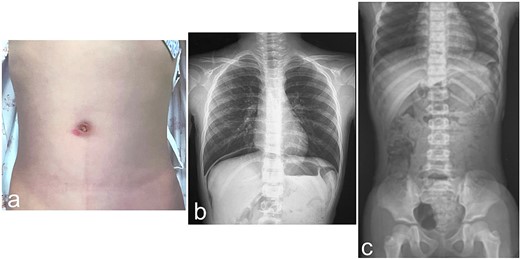

We present our experience with a 6-year-old girl who bruised her abdomen by falling while running with a thermos bottle (water bottle) hanging diagonally across her neck and left shoulder and crossing in front of her body. She went to school with a bruise on her abdomen, but 2 h after the injury she vomited and felt unwell; she was then rushed to the hospital. At the time of examination, her heart rate was 90 beats/min, her blood pressure was 110/62 mm Hg, her respiratory rate was 18 breaths per minute, her oxygen saturation was 98%, and her temperature was 36.6°C. Her abdomen was diffusely tender, but focused assessment with sonography for trauma was negative. She was kept for observation, but her symptoms did not improve. Plain abdominal CT was performed 3 h after the injury and revealed free air in the abdominal cavity, suggesting intestinal injury from blunt trauma. The whole pancreas was checked, but no obvious pancreatic injury was noted. Laboratory assessment showed a white blood cell (WBC) count of 33 200/μL, red blood cell (RBC) count of 4.82 × 106/μL, hemoglobin (Hb) of 13.1 g/dL, hematocrit (Ht) of 40.0%, a platelet count (Plts) of 436 × 103/μL, aspartate transaminase (AST) of 49 IU/L, alanine transaminase (ALT) of 13 IU/L, total bilirubin (T-Bil) of 0.4 mg/dL, and C-reactive protein (CRP) of 0.05 mg/dL (Table 1). She was transferred to our hospital 5 h after the injury. Abdominal examination on admission revealed a bruise and redness at the umbilicus (Fig. 1a), as well as diffuse signs of peritoneal irritation and muscular guarding. Upright chest X-ray showed free air in the right subdiaphragmatic region, but supine abdominal X-ray was normal (Fig. 1b and c). Laboratory assessment was repeated at our hospital and showed a WBC count of 28 960/μL, RBC count of 4.72 × 106/μL, Hb of 13.1 g/dL, Ht of 39.4%, Plts of 384 × 103/μL, AST of 48 IU/L, ALT of 12 IU/L, T-Bil of 0.5 mg/dL, amylase (AMY) of 63 IU/L, and CRP of 0.16 mg/dL (Table 1). Laparoscopic surgery was performed to assess the intestinal injury caused by blunt trauma. A transumbilical vertical incision was made, and the laparoscope was introduced. There were no apparent injuries of the liver and spleen, but there was bile leakage in the right upper quadrant, suggesting injury to the duodenum. However, further examination showed no injury to the duodenum and only the head of the pancreas was observed, but no damage was found. Bloody ascites was observed in the pelvis; biochemical analysis of the ascitic fluid revealed a T-Bil of 1.7 mg/dL and AMY of 6274 IU/L (Table 1). The small intestine was pulled out through the laparoscopic incision to confirm its integrity. There was no apparent injury on the ileocecal side, but there was a perforation on the oral side (Fig. 2a). The perforation was temporarily sewn, and the intestine was returned to the abdominal cavity. The site of injury was determined to be the jejunum, adjacent to the ligament of Treitz and two intestinal serosal injuries were also noticed (Fig. 2b). Two intestinal serosal injuries were repaired, and the perforated portion of the intestine was resected and anastomosed (Fig. 2c). After washing out the abdominal cavity, drains were placed under both hemidiaphragms and in the pelvis. The patient was allowed to begin oral intake on the sixth postoperative day. The drains were removed, blood testing was repeated to confirm return to normal values, and the patient was discharged on the 11th day following an uneventful postoperative course.

Physical and radiologic findings. (a) Abdominal photograph shows a bruise and redness at the umbilicus. (b) Upright chest X-ray shows free air in the right subdiaphragmatic region. (c) Supine abdominal X-ray shows no relevant findings.